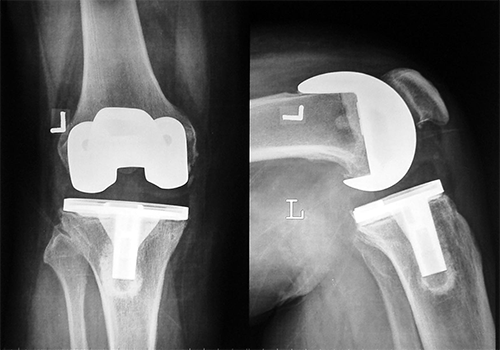

Case:1 TKR

Arthroscopy Surgeon in Ahmedabad

Pre-Op Lateral

Pre-Surgery

Post-Surgery

Case:2 TKR

Pre-Op AP

Post-Op